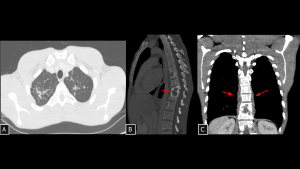

Fig 19: Case 20 – Paravertebral Lesions in IgG4-Related Disease:

Paravertebral lesions with soft-tissue attenuation were identified on CT and radiography, extending anteriorly and to the right of the thoracic vertebral bodies (B and C), without sclerotic or lytic bone changes. The lesions encased the intercostal vessels (A) without causing compression or infiltration.

The imaging findings were suggestive of IgG4-related paravertebral disease, later confirmed by biopsy.

SYSTEMATIC APPROACH: 1. Age: Middle-aged to Elderly males. | 2. Morphology: Diffuse soft-tissue thickening ("Rind-like"). | 3. Enhancement: Homogeneous delayed enhancement. | 4. Relevant Anatomical Relationships: Paravertebral/Periaortic; encases vessels without luminal stenosis.

Fig 20: Case 21 – Paravertebral mediastinal metastasis:

A 35-year-old patient with an atypical lipomatous tumor of the right leg (previously operated, with local recurrence demonstrated on MRI (A) developed a heterogeneous solid lesion in the paravertebral mediastinum (arrow in B). The lesion was located anterior and left to the thoracic vertebral bodies and contained foci of fat attenuation (arrows in B and C), consistent with secondary involvement.

SYSTEMATIC APPROACH: 1. Age: Adults / Elderly (History of primary malignancy). | 2. Morphology: Osteolytic bone destruction or conglomerate nodal mass. | 3. Enhancement: Variable (depends on primary). | 4. Relevant Anatomical Relationships: Destroys vertebral body or invades adjacent organs.